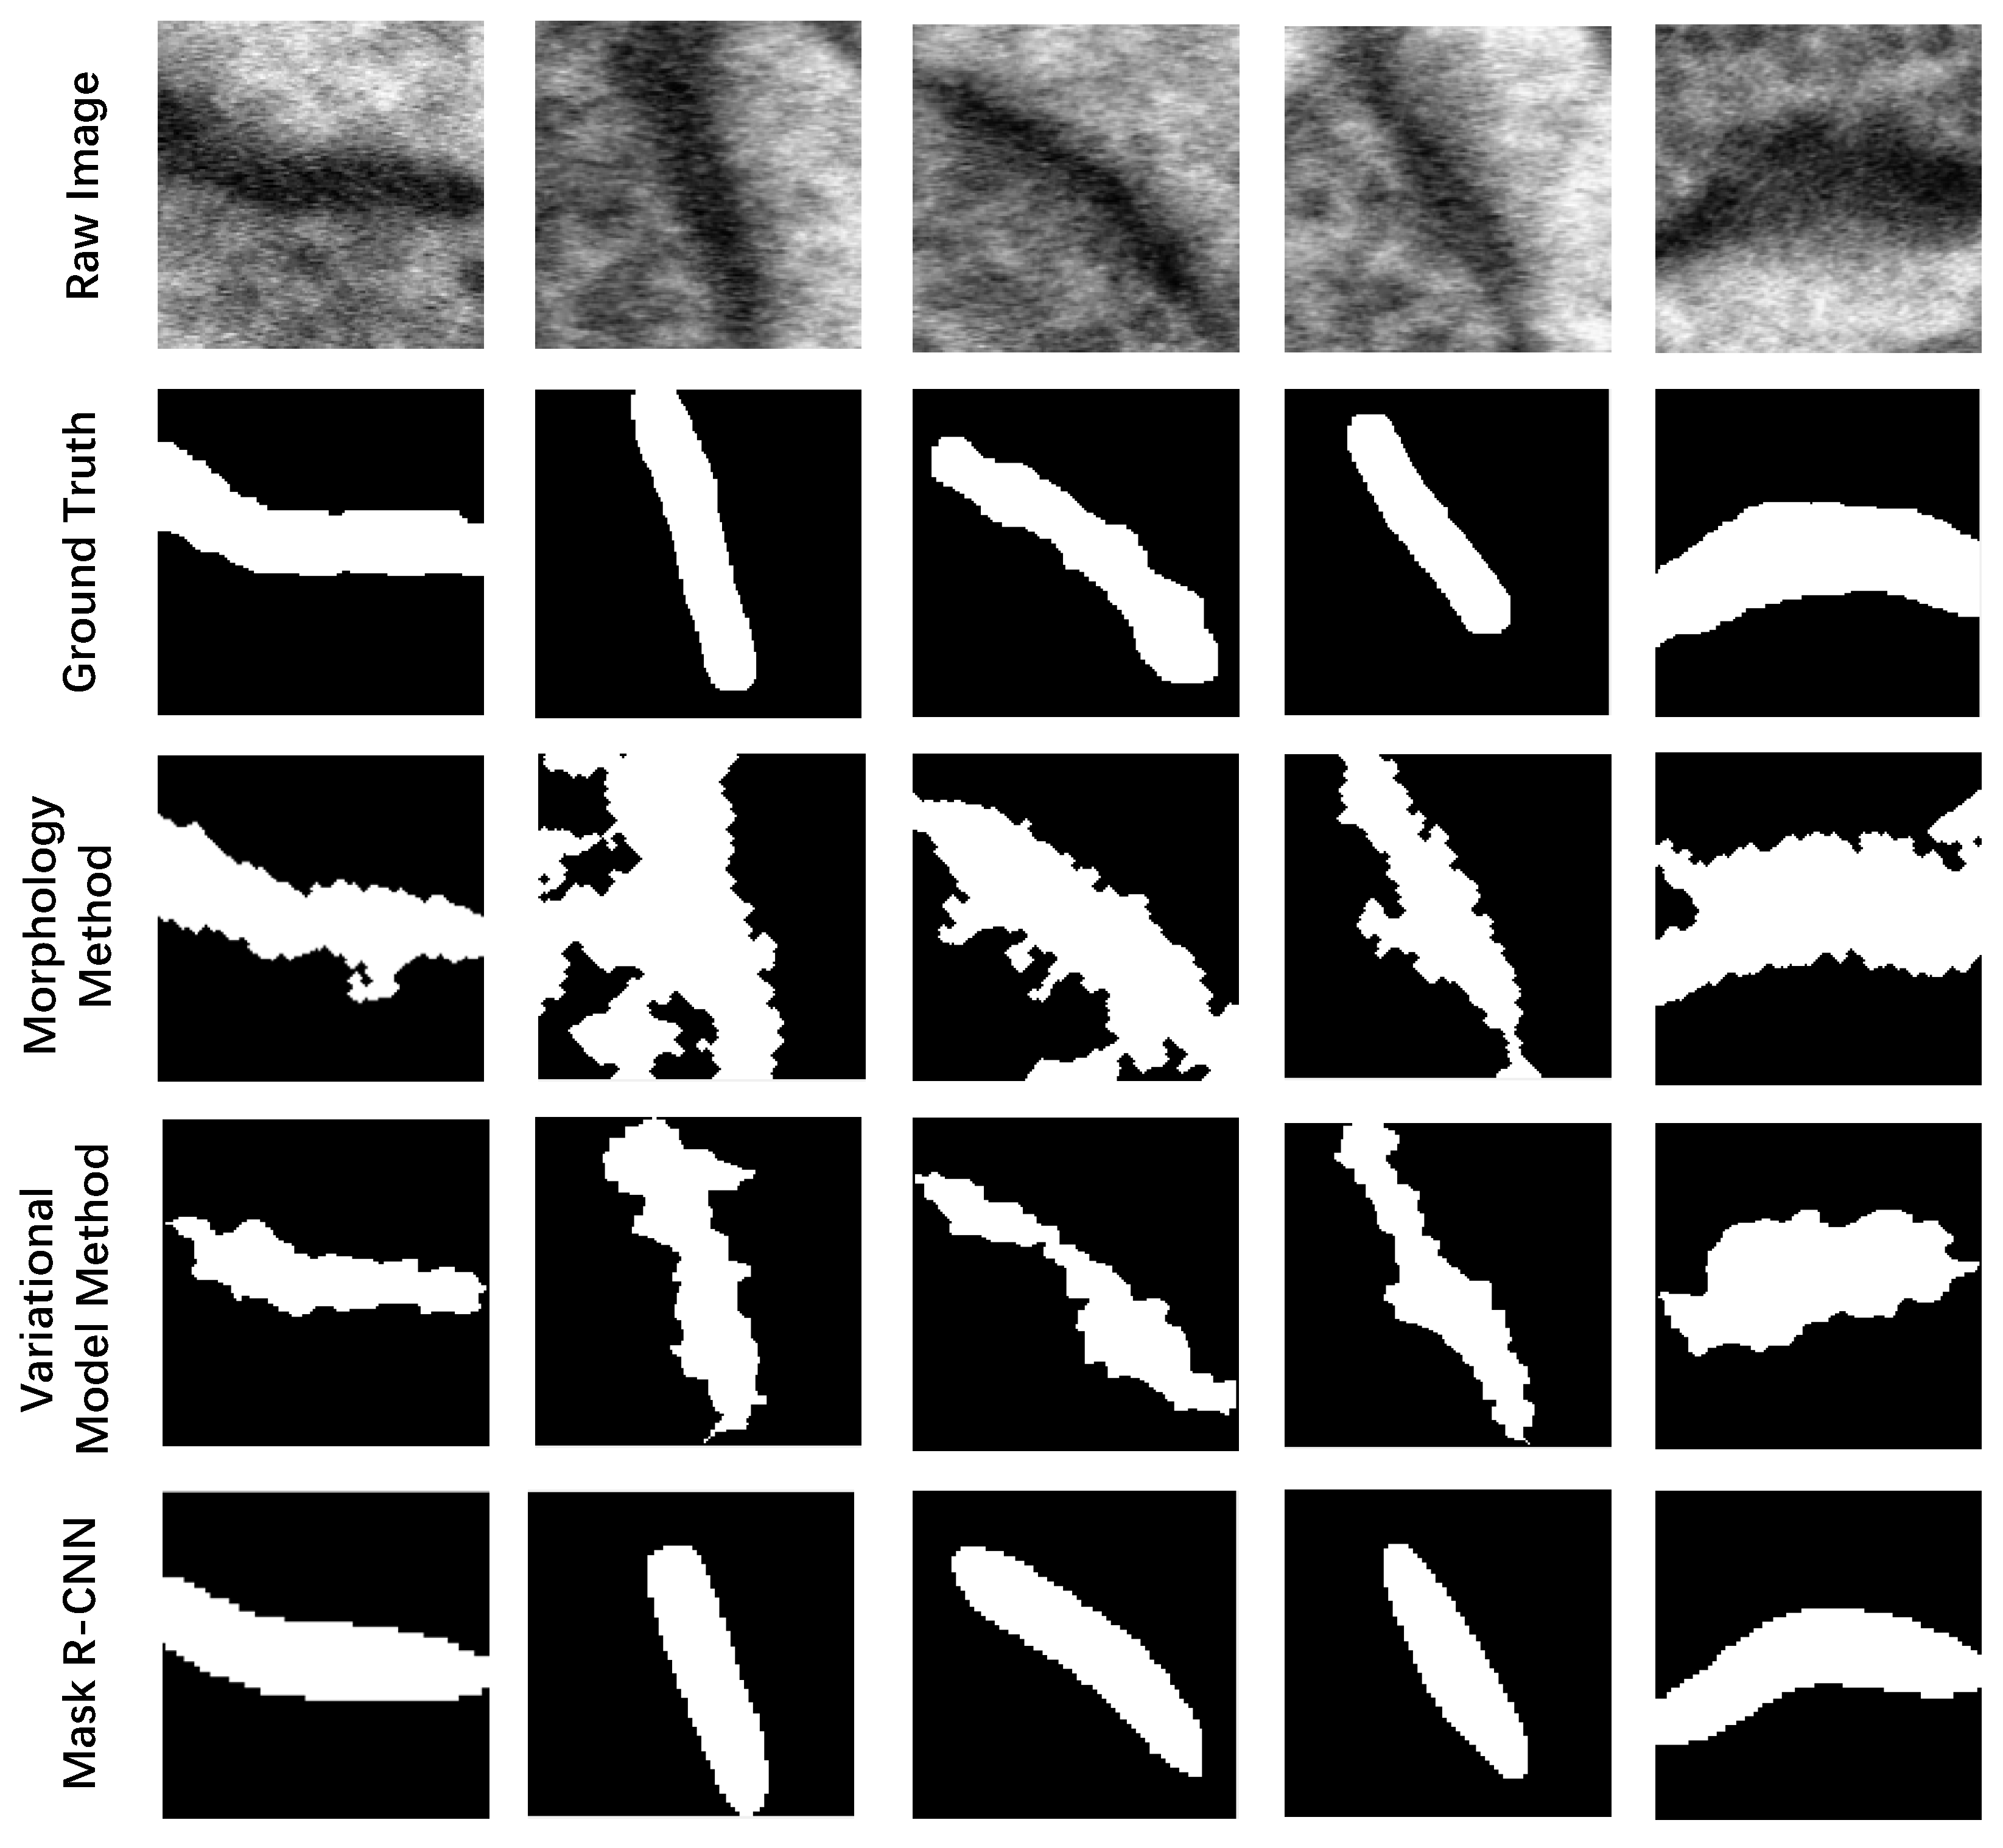

3.2.1. Detection and Segmentation with Mask R-CNN

| Morphology Method | Variational Model Method [34,35,36] | Mask R-CNN | |

|---|---|---|---|

| J(Synapses, Ground truth) | 19.21% | 18.49% | 65.55% |